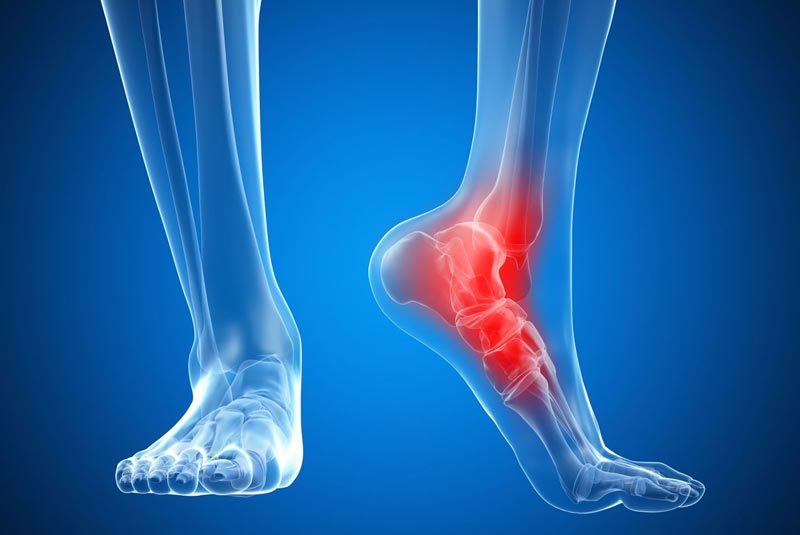

Έχει 5ετή μετεκπαίδευση και εργασία στο Ηνωμένο Βασίλειο ως ειδικός Ορθοπαιδικός Χειρουργός. Έχει εργαστεί στα Ορθοπαιδικά Τμήματα των Νοσοκομείων Southampton University Hospitals NHS Trust, Leeds Teaching Hospitals NHS Trust και στο Northampton General Hospital NHS Trust, με υποεξειδίκευση στη Χειρουργική Ώμου, Γόνατος, Ισχίου, Ποδοκνημικής & Άκρου Ποδός, Ώμου & Αγκώνος και Γενικού Τραύματος Ενηλίκων και Παίδων.

Κατά τη διάρκεια της εργασίας του στο Ηνωμένο Βασίλειο εκπαιδεύτηκε σε σύγχρονες τεχνικές Αρθροσκοπικής Χειρουργικής και Επανορθωτικής Χειρουργικής Ισχίου, Γόνατος και Ώμου. Επιπλέον έχει δώσει πολυάριθμες διαλέξεις και έχει εκπαιδεύσει νεότερους Ορθοπαιδικούς και φοιτητές Ιατρικής. Αξιοσημείωτο και πλούσιο είναι το επιστημονικό του έργο με συμμετοχή σε δεκάδες συνέδρια και σεμινάρια στην Ελλάδα και στο εξωτερικό και έχει πληθώρα προφορικών ανακοινώσεων και δημοσιεύσεων.

Παθήσεις & Θεραπείες